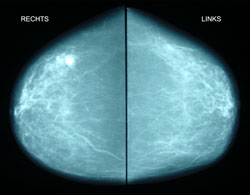

Mammographie (Brustuntersuchung durch Röntgendiagnostik)

Die Mammographie ist eine bewährte und seit Jahrzehnten bekannte und geübte Methode zur frühen Entdeckung von Tumoren in der Brust. Seit einigen Jahren wird sie für Frauen zwischen 50 und 69 Jahren als "Screening-Mammographie" angeboten. Vorteil des Screenings ist die Kostenfreiheit für gesetzlich versicherte Frauen, Nachteil ist die mangelnde Kooperation zwischen den Screeningstellen und den niedergelassenen Ärzten. Ihr Frauenarzt bekommt keinen Befund!

Mammographie und Ultraschall sind keine konkurrierenden Methoden, sondern sie ergänzen sich. Am sichersten kann man ein Karzinom ausschließen, wenn bei keiner Methode ein verdächtiger Befund erhoben wurde. Für Frauen unter 40 Jahren ist die Mammographie als Früherkennungsmethode ungeeignet.

Das linke Bild unten zeigt Mammographieaufnahmen von beiden Brüsten, "rechts" mit einem hellen Fleck, links unauffällig. Die rechte Aufnahme unten zeigt eine Vergrößerung des hellen Flecks, der unscharf begrenzt ist und sich bei der weiteren Untersuchung als Karzinom erwies. Dieser Tumor war übrigens nicht tastbar. Er wurde anläßlich einer Vorsorgeuntersuchung durch Ultraschall entdeckt. Die 80jhr. Patientin wurde brusterhaltend operiert und ist seither gesund.